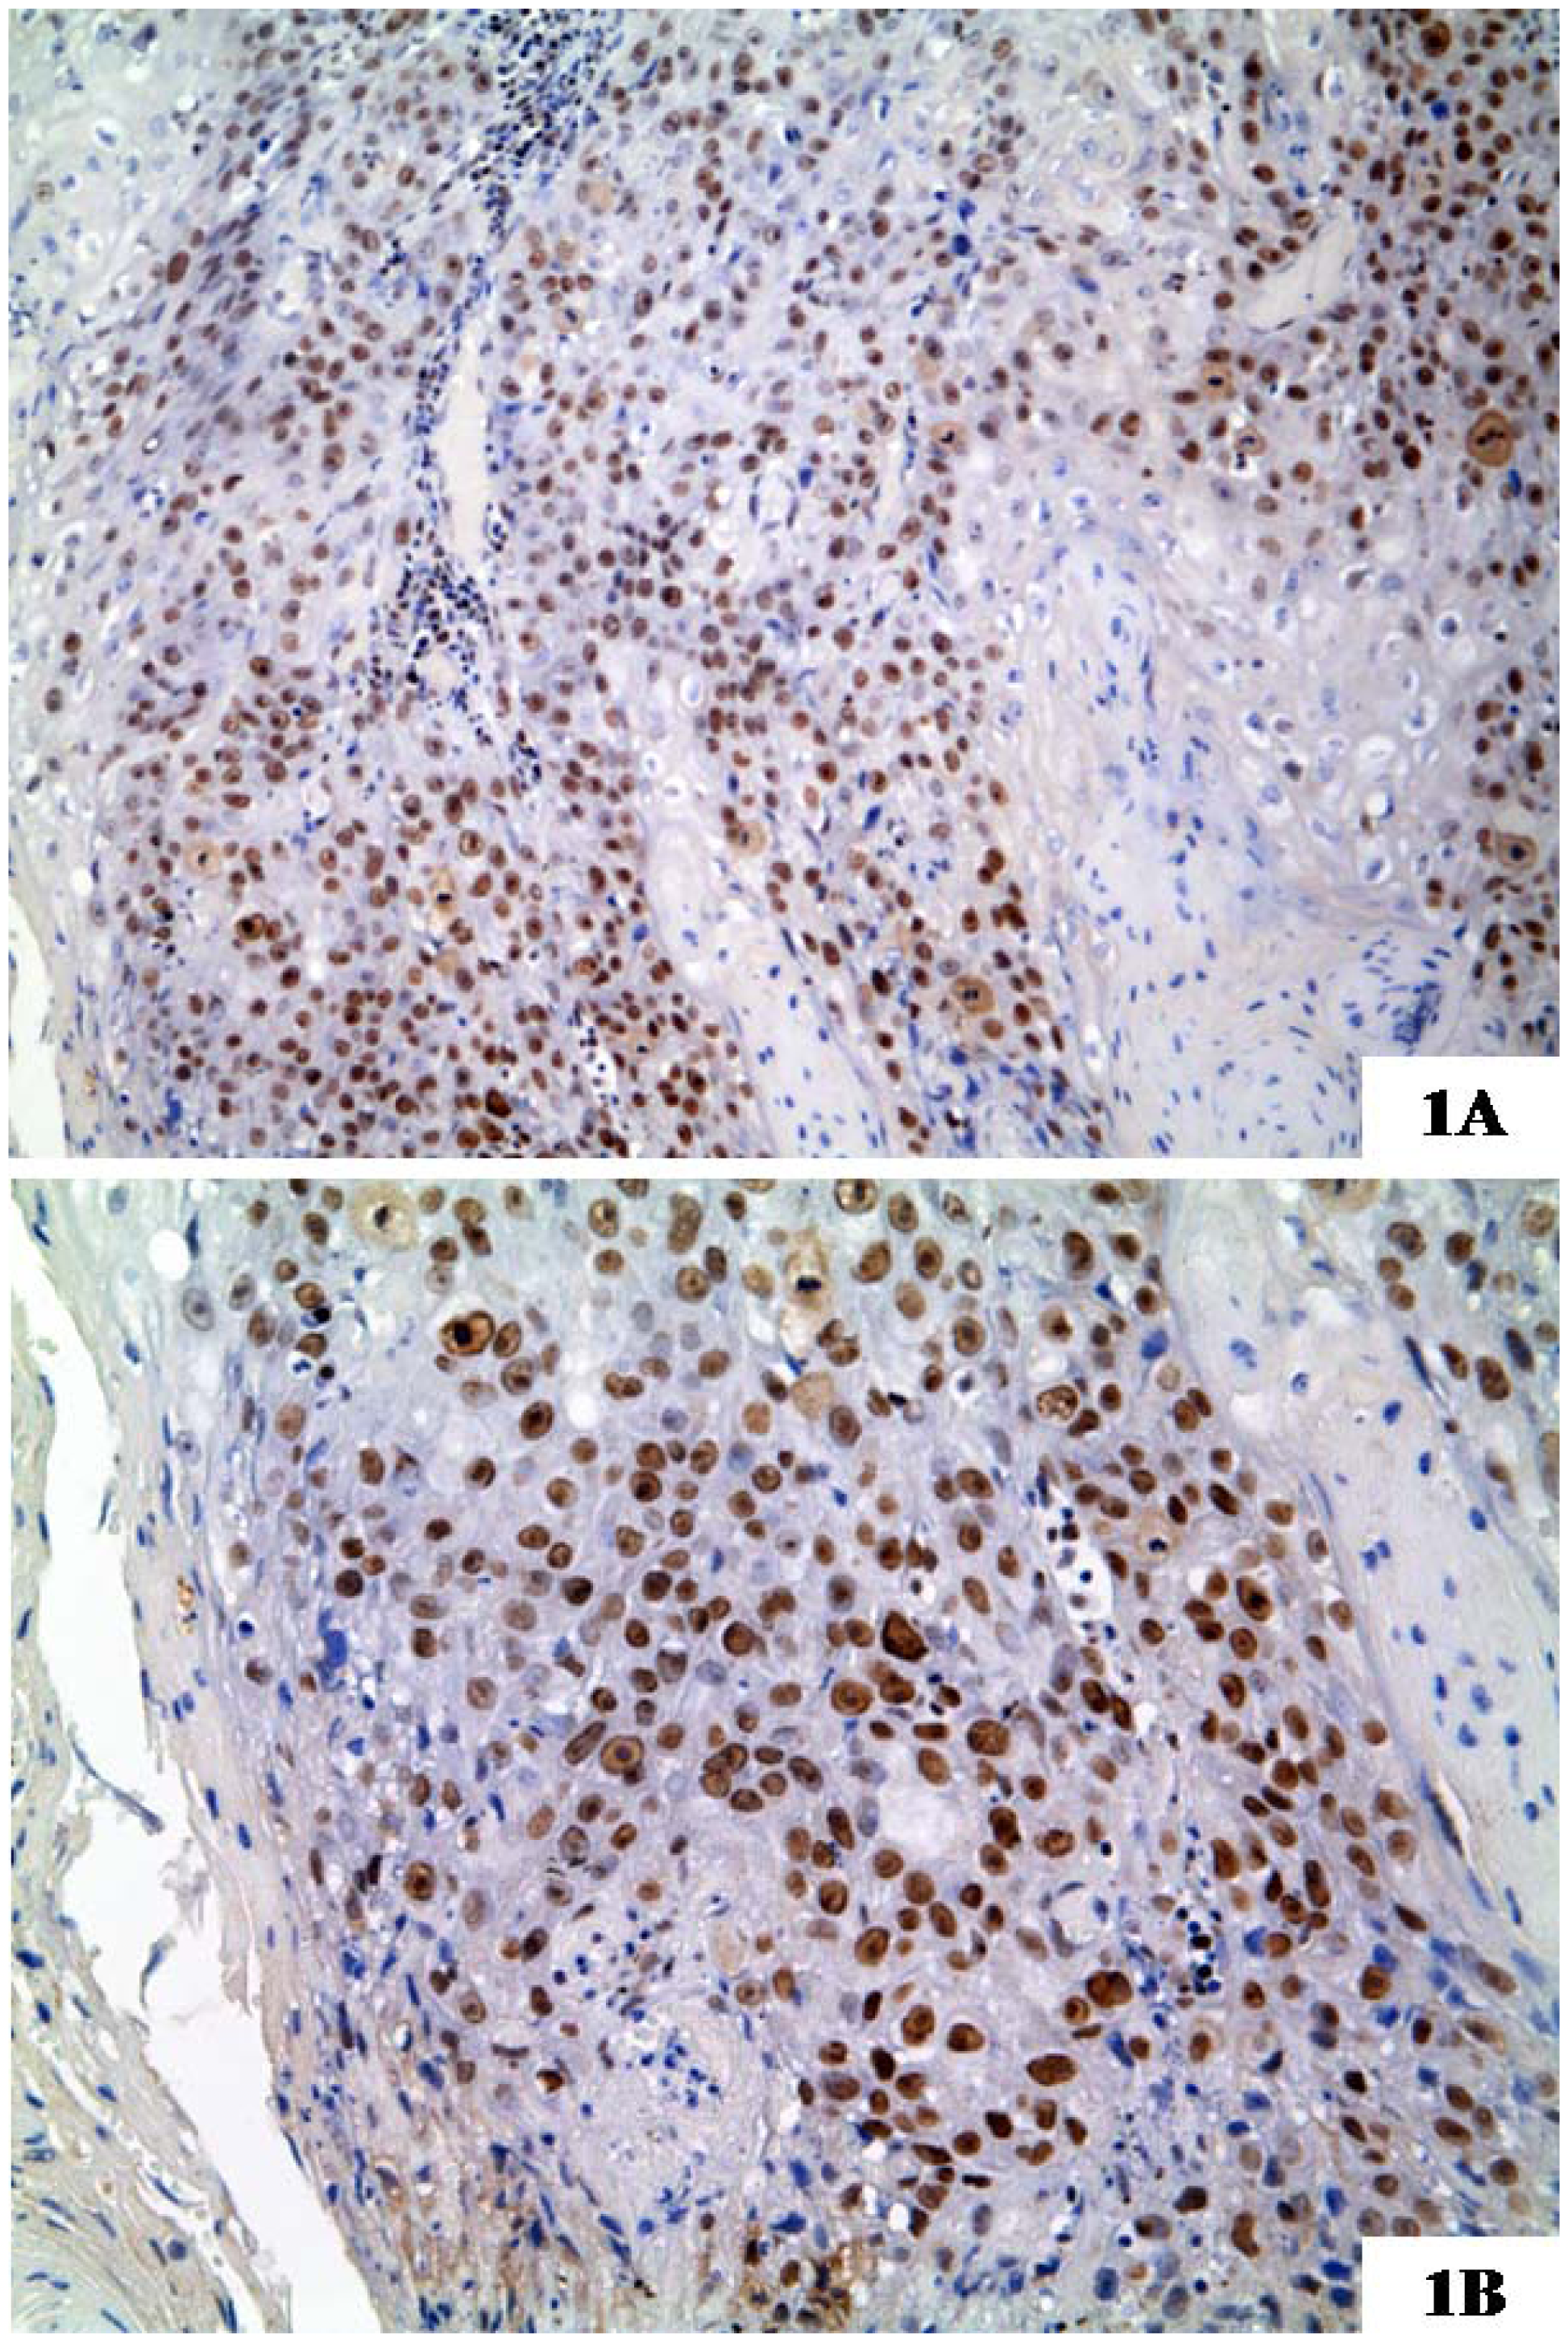

- Polo, S.E.; Theocharis, S.E.; Klijanienko, J.; Savignoni, A.; Asselain, B.; Vielh, P.; Almouzni, G. Chromatin Assembly Factor-1, a marker of clinical value to distinguish quiescent from proliferating cells. Cancer Res 2004, 64, 2371–2381. [Google Scholar]

- Staibano, S.; Mascolo, M.; Rocco, A.; Lo Muzio, L.; Ilardi, G.; Siano, M.; Pannone, G.; Vecchione, M.L.; Nugnes, L.; Califano, L.; et al. The proliferation marker Chromatin Assembly Factor-1 is of clinical value in predicting the biological behaviour of salivary gland tumours. Oncol. Rep 2011, 25, 13–22. [Google Scholar]

- Staibano, S.; Mignogna, C.; Lo Muzio, L.; Mascolo, M.; Salvatore, G.; Di Benedetto, M.; Califano, L.; Rubini, C.; de Rosa, G. Chromatin assembly factor-1 (CAF-1)-mediated regulation of cell proliferation and DNA repair: A link with the biological behaviour of squamous cell carcinoma of the tongue? Histopathology 2007, 50, 911–919. [Google Scholar]